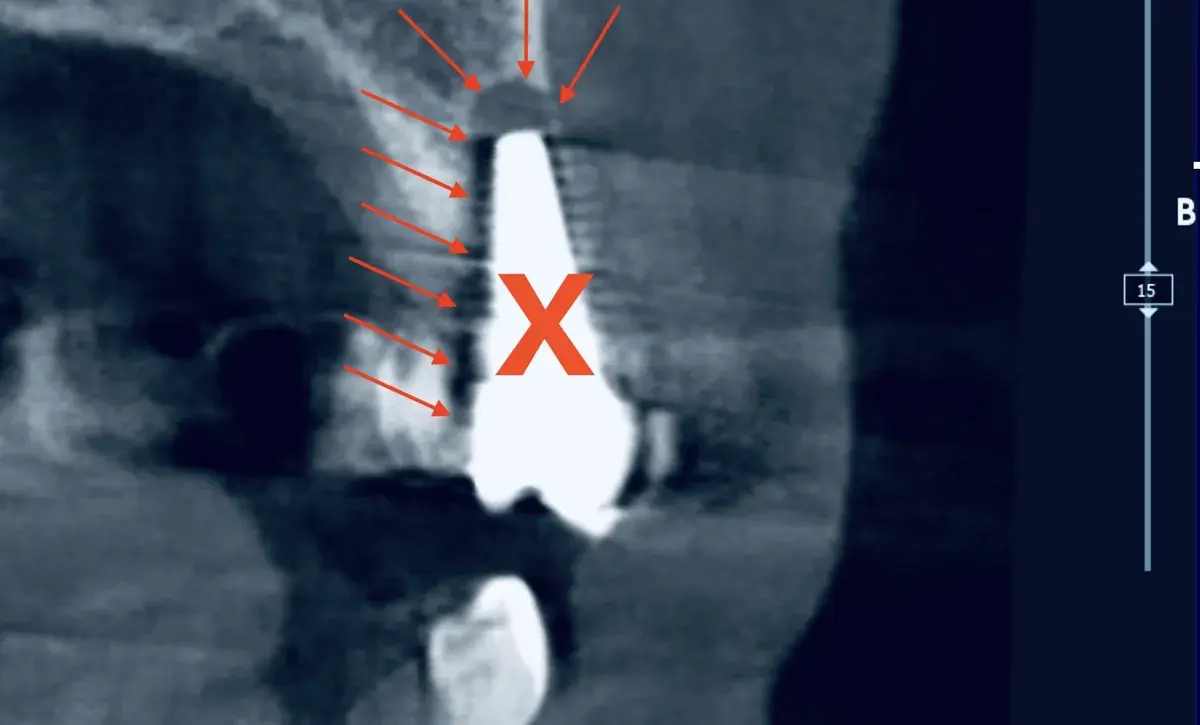

Caso clinico di peri-implantite severa trattata con decontaminazione TST (Ten Second Technique) e rigenerazione ossea guidata. Follow-up a 2 anni.